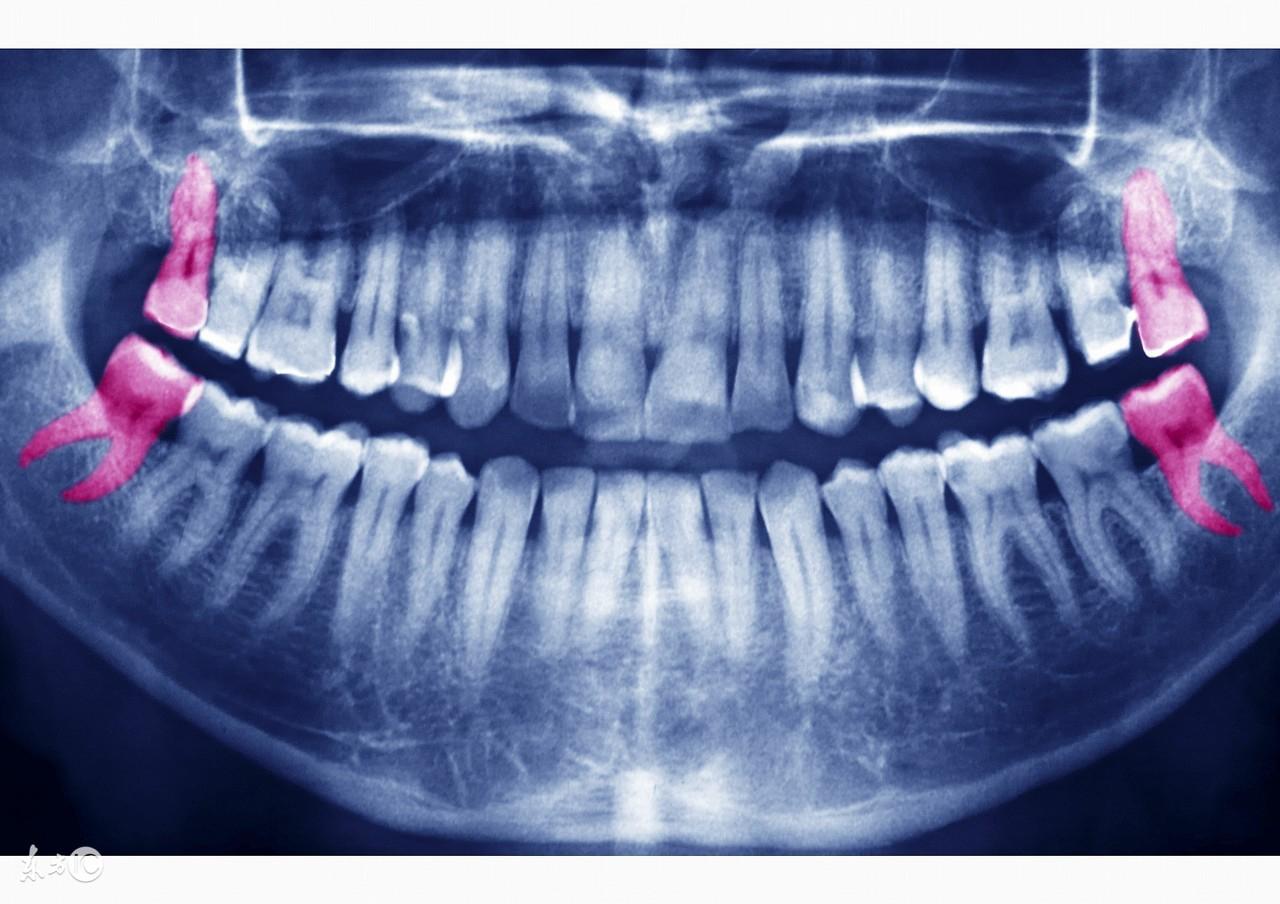

“削骨瘦脸多见的方式是下颌角整形术,使用专业的磨具将下颚角骨头外层磨薄,从而缩减宽度,尤其适合方形脸。如果选择有资质的综合性三甲医院,削骨瘦脸十分,风险基数很小。”

你的骨重为 37 钱。所谓的磨骨手术就是下颌角手术,任何手术都是有风险的,要想将风险降到低首先选择正规专业的医院。下颌角肥大的手术方法

我院目前采用的是口腔内入路,具体如何瘦脸也要针对不同脸型和下颌角类型采取不同的截骨手术方法,截骨准确,可进行下颌角、下颌缘联合截骨,对由于下颌骨过大造成的大脸型,长脸型,大四方脸等有特殊改良果,使脸型变小,变得更秀气,手术中配合冷光源和特殊器械,手术时间短,术后不留任何体表瘢痕;口腔内截骨还可同时去除咬肌肥大

、颊脂肪垫,使瘦脸果更。